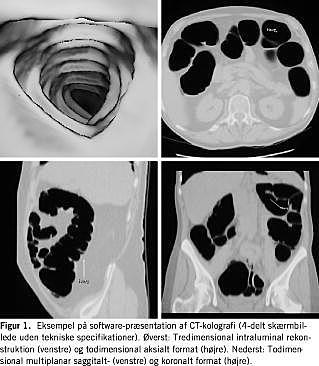

Procedure

Proceduren består i tre trin: udrensning, skanning og billedanalyse. En optimal undersøgelse forudsætter optimal udrensning, der bedst opnås med dinatriumphosphat [2]. Hyoscinbutylbromid kan anvendes for at optimere udspiling og mindske bevægeartefakter, men der bruges hverken smertestillende eller beroligende medicin. Der skannes i både ryg- og bugleje, fordi ændringen i fordeling af luft og evt. restvæske synes at bidrage omkostningseffektivt til diagnostikken. Oftest er det primært de »almindelige« aksiale todimensionale billeder, der gennemses. Men analysen må fortages på en arbejdsstation, hvor der kan suppleres med todimensionale multiplanare reformaterede (saggitale og koronale) billeder og evt. kombineres med tredimensionale endoluminale rekonstruktioner i tilfælde af diagnostiske problemer (Figur 1 ). Hvis hele datasættet analyseres interaktivt i tredimensionalformatet, simuleres en sort-hvid koloskopi - en »virtuel koloskopi«. Denne analysemetode er imidlertid mindre omkostningseffektiv [3] og benyttes sjældent. Bl.a. derfor er betegnelserne CTK og MRK mere præcise.